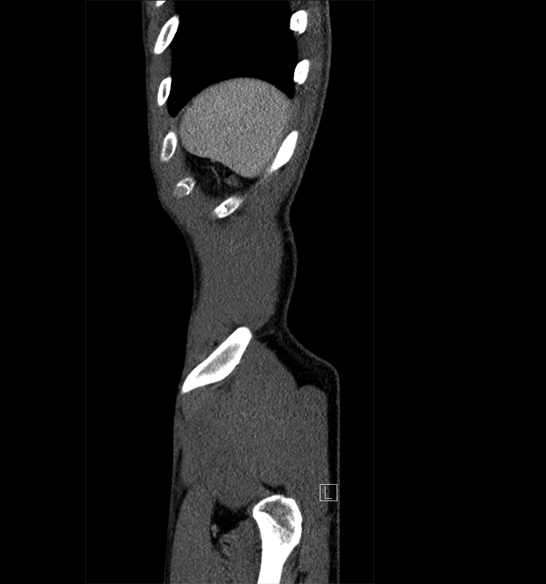

Body

Covers abdominal CT anatomy.